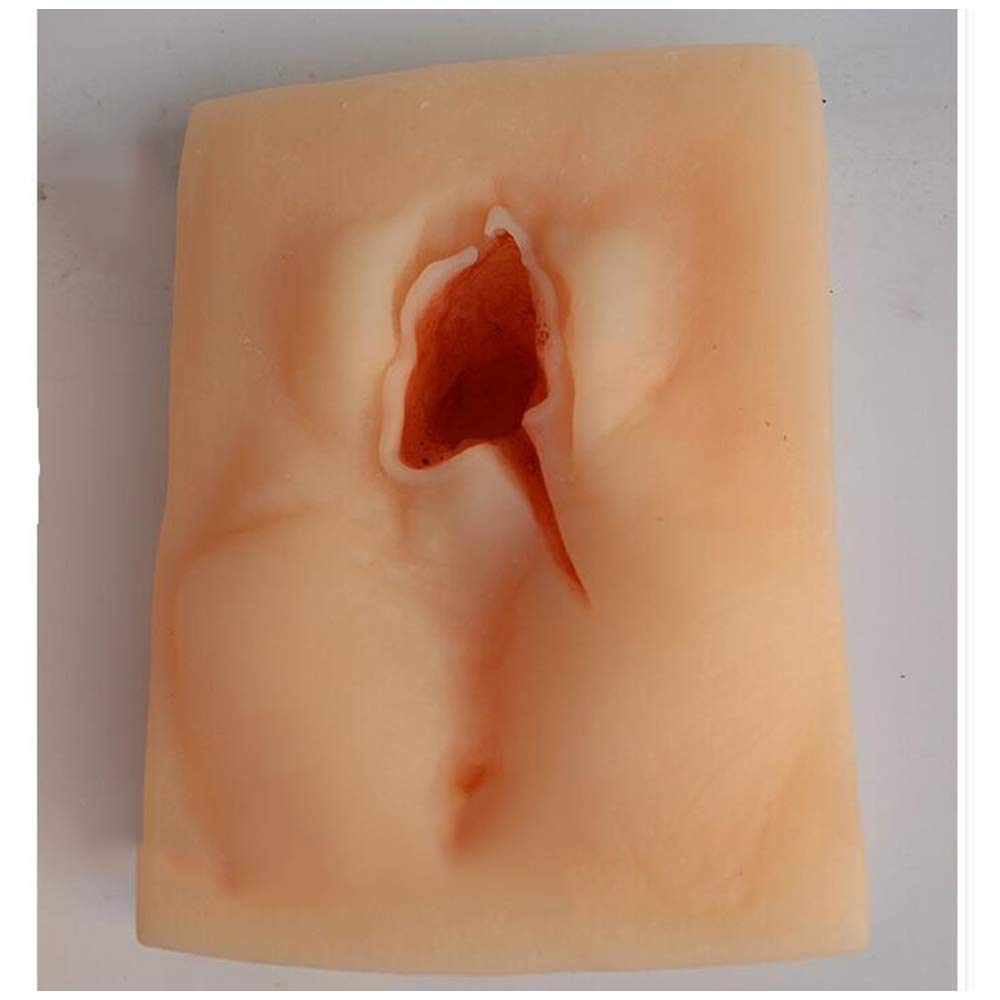

🩺 Elevate your suturing skills with lifelike precision and zero downtime!

The oBlosdhVulva Suture Practice Model is a high-fidelity female perineal incision training tool featuring three distinct incision sites. Made from environmentally friendly PVC, it offers realistic skin texture and durability for repeated use. Ideal for medical students and professionals, it requires no assembly and supports efficient, hands-on learning in gynecological suturing techniques.